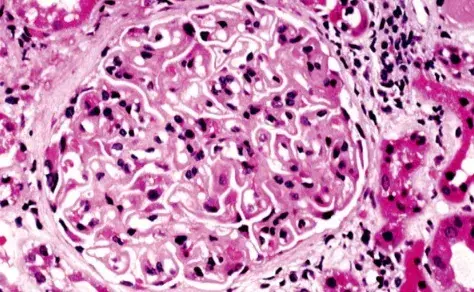

É possível identificar um glomérulo com quebra ruptura da MBG, com crescente celular no espaço de Bowman (seta branca), célula gigante multinucleada (estrela) e ruptura da cápsula de Bowman (seta preta) (PAS; 400×). PAS, ácido periódico-Schiff.

A biópsia renal revelou GN crescêntica necrotizante difusa sem hipercelularidade endocapilar. Alguns raros glomérulos continham células gigantes multinucleadas.

A avaliação da microscopia de luz pode ajudar na diferenciação de casos de **GN por anti-MBG** de casos **GN-ANCA**, já que na GN anti-MBG não observamos hipercelularidade endocapilar e pode ser identificado a presença de células gigantes multinucleadas, estas células gigantes multinucleadas resultam a natureza explosiva e a rápida destruição dos glomérulos observadas em anti-MBG

Desta forma, a presença de lesões crescentes temporalmente semelhantes e células gigantes multinucleadas na microscopia de luz (MO) pode ajudar no diagnóstico precoce.